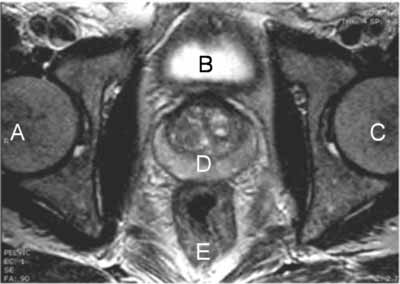

RMN de la próstata - examen normal. Proyección hacia arriba desde los pies hacia la cabeza del paciente. (A: cadera derecha, B: vejiga, C: cadera izquierda, D: próstata, E: recto)

Nota: Las imágenes se muestra para fines ilustrativos. No trate de sacar conclusiones comparando esta imagen con otras en el sitio. Solamente los radiólogos calificados deben interpretar las imágenes.